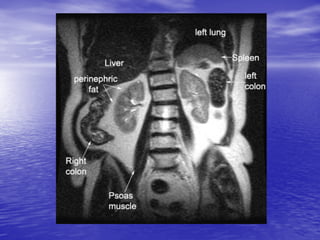

109 Pt A -Axial VIBE - Kidney and Retroperitoneum Plate 29 The kidneys are retroperitoneal structures that reside at the level of T12 to L3, with the right typically being lower than the left due to the presence of the liver. It is encapsulated and housed, along with the adrenal glands, within the perirenal space. This space is surrounded by Gerota’s fascia. The anterior and posterior pararenal space surround Gerota’s fascia with an additional layer of adipose tissue (see slide 74 for a more detailed look at the retroperitoneum). These retroperitoneal locations have clinical relevance when staging for renal cell carcinoma or assessing for renal infection or trauma. In terms of relations, the kidney is well connected, coming into contact (through peri- and pararenal spaces) bilaterally with the adrenals and diaphragm superiorly and the quadratus lumborum and psoas muscles inferomedially. On the right side the kidney is adjacent to the liver, duodenum, and ascending colon. On the left side the kidney is in contact with spleen, stomach, pancreas, jejunum, and descending colon. Posterior pararenal space Perirenal space Kidney Perirenal space Anterior pararenal space

• 110.

110 Axial VIBE -Ureter Transverse colon Deep back muscles Ureter Hepatic flexure Quadratus lumborum Psoas muscle Superior mesenteric artery Small bowel Superior mesenteric vein Fundus of gallbladder Anterior pararenal space* Posterior pararenal space* Perirenal space* Lumbar vessels Inferior vena cava Aorta Flank stripe* Duodenum * Marked structures of retroperitoneum will be discussed in the following slide. Plate 30

• 111.

111 Axial VIBE -Lower Poles of Kidneys Transverse colon Quadratus lumborum Psoas muscle Small bowel Inferior vena cava Fundus of gall bladder Aorta L. ureter Erector spinae Liver R. ureter Plate 33

• 112.

112 Coronal Plane -VIBE Reformatted Adrenal Glands Thoracic aorta Hepatic vein Hepatorenal recess R. kidney Spleen Psoas m. L. kidney Splenic v. Right renal arteries L. renal arteries Inferior vena cava R. adrenal gland L. adrenal gland Gastric cardia Abdominal aorta Plate 53